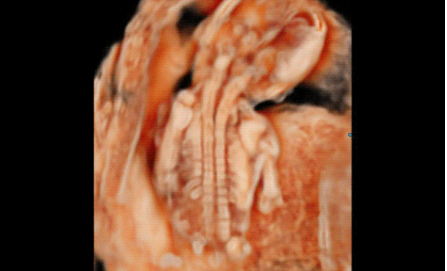

Hera i 10繼承并升級了全球首款5D超聲“三星麥迪遜WS80A”的“晶體結(jié)構(gòu)”成像理念,即將CrystalBeam?波束形成技術(shù)、CrystalLive?超聲成像引擎、S-Vue Transducer?視覺傳感器集于一身,提供更清晰的圖像。

3D/4D成像方面,Hera i 10通過結(jié)合先進(jìn)的圖像渲染技術(shù),著重加強(qiáng)了邊緣和小結(jié)構(gòu)的可視化能力。